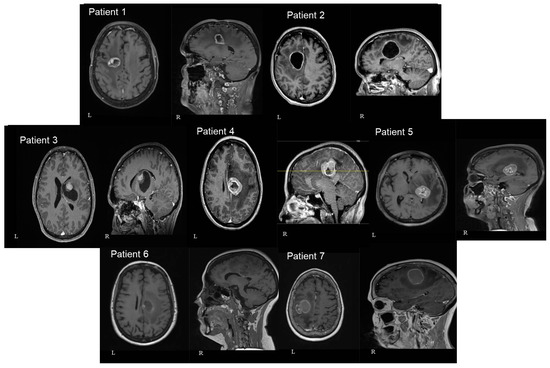

Figure 4.

Axial (left—L) and sagittal (right—R) T1 gad MRI brain images of all seven patients included in our study. In 3 patients the lesion was located at the cingulate gyrus (numbers 2, 4, and 6). In 2 of them, the tumor was centered in the precentral gyrus (numbers 1 and 7). In the final 2 patients, the lesion was centered at the basal ganglia involving the thalamus and the internal capsule (numbers 3 and 5). The number of patients in each image corresponds to the patients mentioned in Table 1.

In three patients the lesion was located at the cingulate gyrus. In two of them, the tumor was centered in the precentral gyrus, and in the final two, at the basal ganglia involving the thalamus and the internal capsule. Four patients had left-sided lesions and three had right-sided lesions. The mean distance between the lesions and the cortex as measured in the preoperative MRIs was 30.9 mm (range: 7 mm–46 mm) (Figure 3 and Figure 4). The mean volume of the included lesions was 13.2 cm3 (range: 3.3–32.6 cm3).